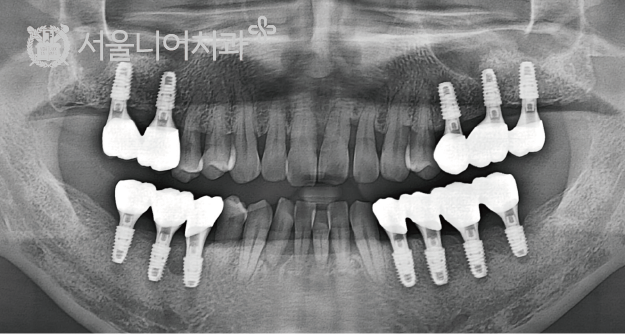

before & after

꼭 필요한 치료만을 권해드리는 서울니어치과의 임플란트 시술 사례

before

after

case 5. 70대 남성 / 잇몸병으로 상실된 다수 치아 / 오스템 SOI 임플란트 8개 / 뼈이식

꼭 필요한 치료만을 권해드리는

서울니어치과의 임플란트 시술 사례

case 1. 전악 임플란트

case 2. 전악 임플란트

case 3. 전악 임플란트

case 4. 전악 임플란트